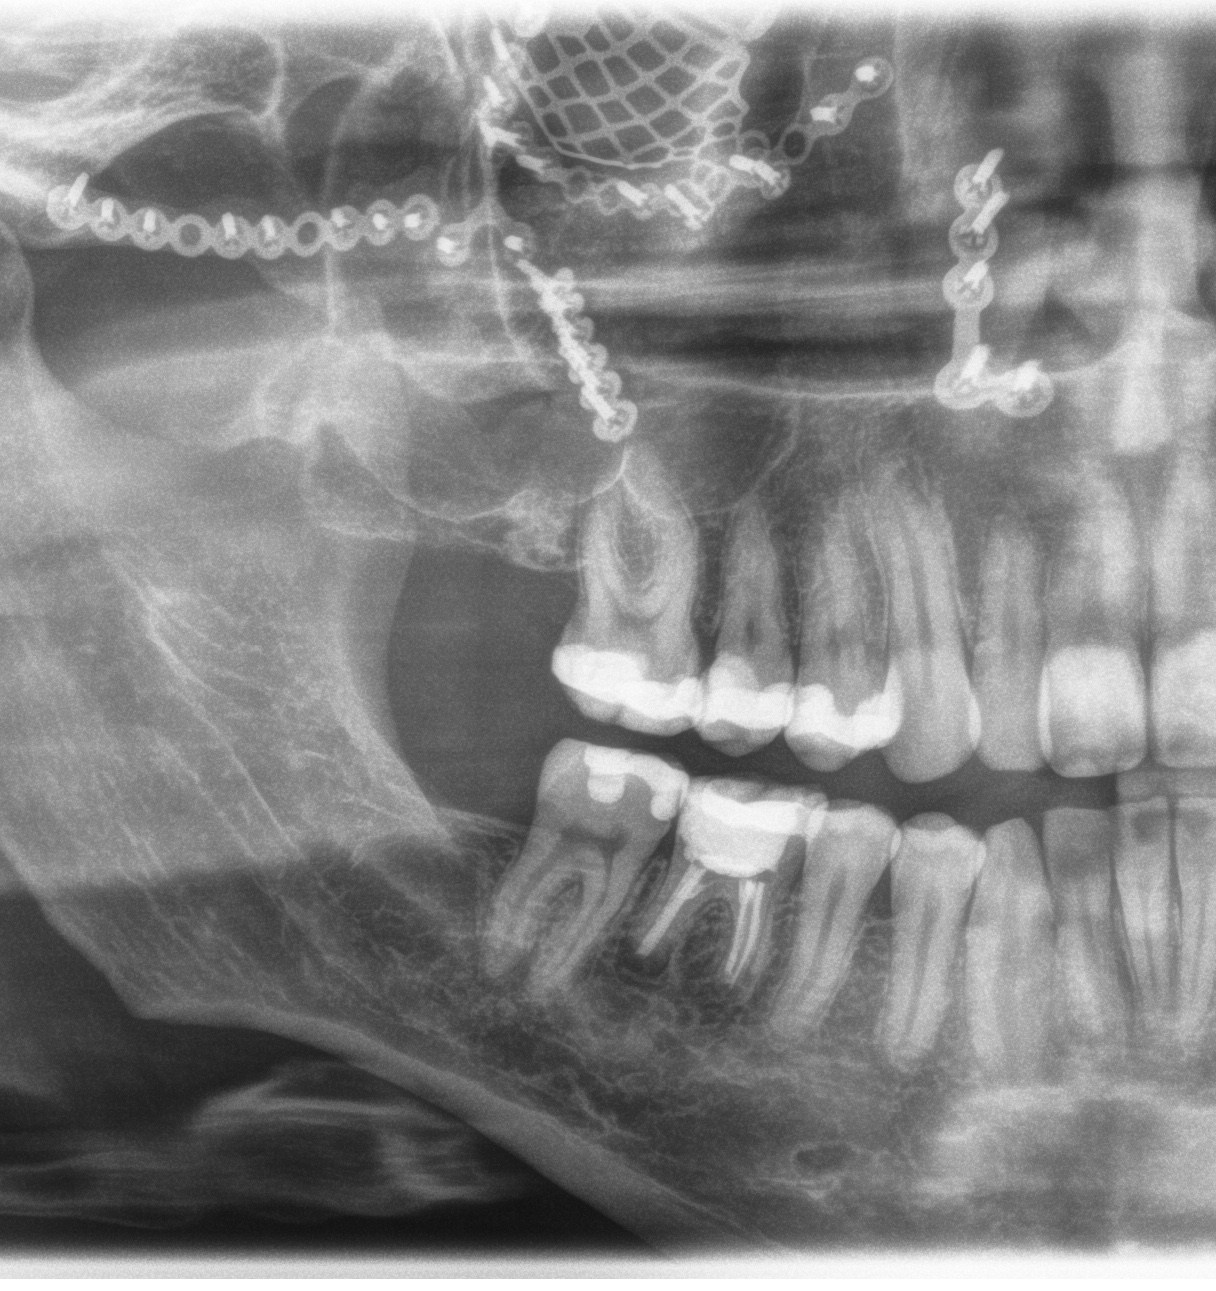

Hier mal ein Auszug wie mein Kopf nun von innen ausschaut.

Eigentlich war das ne Aufnahme beim Zahnarzt, aber da sieht man so schön das Titanmesh unter dem Auge.